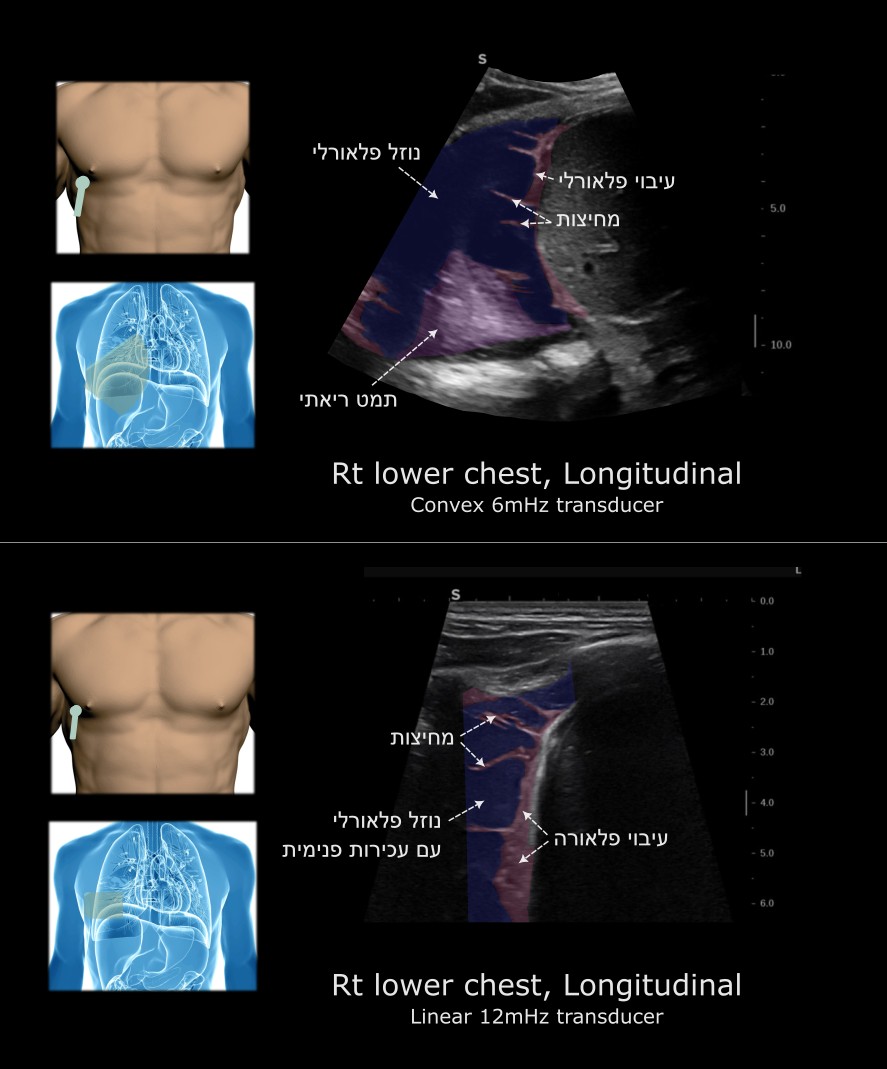

בן 42, קוצר נשימה וחום מזה כשבוע

בבדיקתו: כניסת אוויר מופחתת מימין

מדדים חיוניים: חום מוגבר, טכיקרדי

בבדיקות מעבדה: מדדי דלקת מוגברים

אמפיאמה

* התוכן העכור נצפה טוב יותר במתמר ליניארי ברזולוציה גבוהה